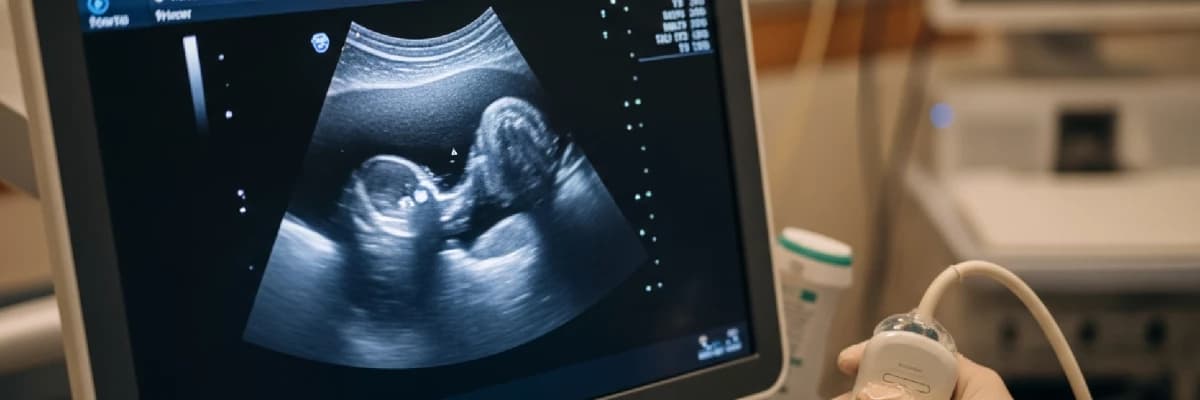

Gebelikte Anomali Taramasının Önemi ve Amaçları

Kadın Hastalıkları ve Doğum Uzmanı Doç. Dr. Türkan Örnek, anne adaylarının sağlıklı bir gebelik süreci geçirmesi ve bilinçli kararlar alabilmesi için anomali taramasının kritik bir rol oynadığını belirtmektedir. Ekonomik ve fiziki şartlar el verdiği ölçüde tüm hamilelerin bu taramadan geçmesi gerektiğini vurgulayan Örnek, anne adayının bebeğin sağlık durumu hakkında önceden bilgi sahibi olmasının önemine dikkat çekmektedir.

Anomali taramasının temel amacı, gebelik süresince olası problemlerin en erken aşamada saptanmasıdır. Toplumda anomali görülme olasılığı %2.4 civarındadır. Bu taramalar her zaman gebeliğin sonlandırılması anlamına gelmez; aksine, doğum sonrası gerekli tedavilerin zamanında planlanmasını ve müdahale edilmesini sağlar.